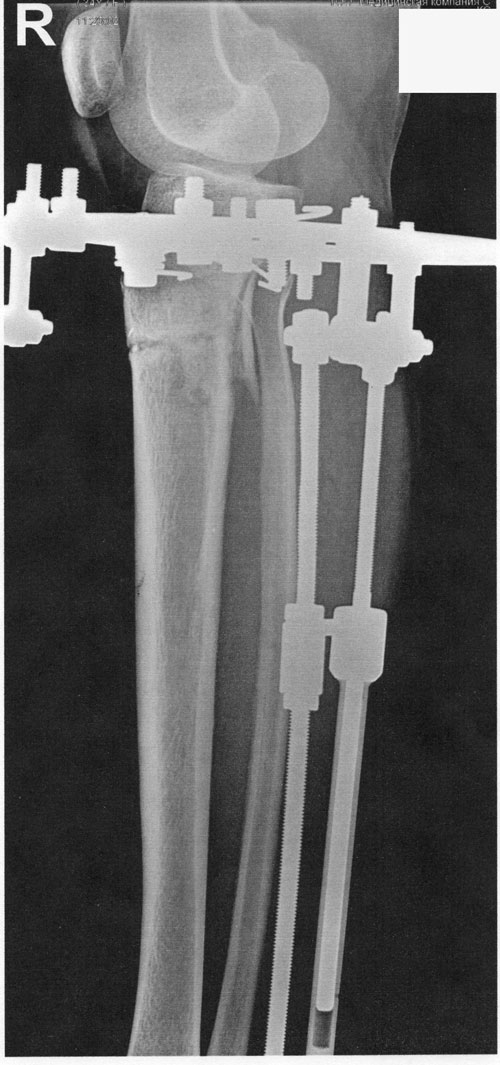

Отправляю вам контрольные рентген-снимки и фото ножек. Со дня снятия прошло 50 дней.

Здравствуйте, Наталья! По рентгену, всё отлично! разрешено всё без ограничений! Исключить: беременность в течении первых 6 месяцев.

Спасибо за фото ножек! не забывайте про наш форум, пишите отзывы, выставляйте фото красивых ножек! Это для нас важно, мы гордимся своей работой!